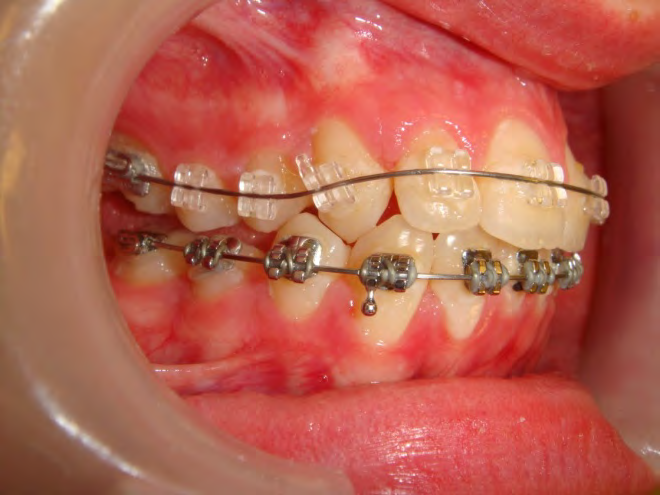

All of the patients below had been told they required extractions by orthodontists, some insisting that they could not be treated without extractions.

They were all treated without extractions, head gear or facemasks at Vakresmil and represent just a small sample of cases treated between 2004–2014.

The patient below had severe crowding of both upper canines and the lower right 5. The upper 4’s and 2’s were actually in contact.